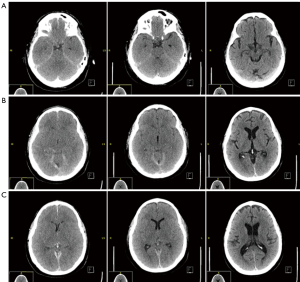

A non-contrast head computed tomography (CT) obtained at the time demonstrated posterior fossa crowding with effacement of the ambient cisterns, and a diffuse appearance of brain edema with slit like ventricles. There was also a small tentorial SDH and small amount of intraventricular hemorrhage. There was no evidence of bony fractures or complications from head tong sites (Figure 2). There had been no episodes of hypoxia during or after the procedure.

Beta-2 transferrin levels (a highly sensitive and specific measure of CSF) from drain fluid were negative postoperative days 1–4, with total daily drain output 652, 147.5, 216, and 98 mL but when there was a sudden increase in serous quality drainage in the subfascial drain on postoperative day 5 with the patient reporting a minor eye pain with output of 158 mL. Another beta-2 transferrin lab was sent and this time it was positive, as a result the drain was pulled and the drain site was oversewn. The patient passed head of bed trials and never experienced proto-typical symptoms of CSF leak. Repeat head CT postoperative day 4 demonstrated marked improvement in ventricular caliber and cisternal effacement, slightly decreased intraventricular blood products but no other significant changes with regards to subdural and parafalcine hemorrhages (Figure 3).